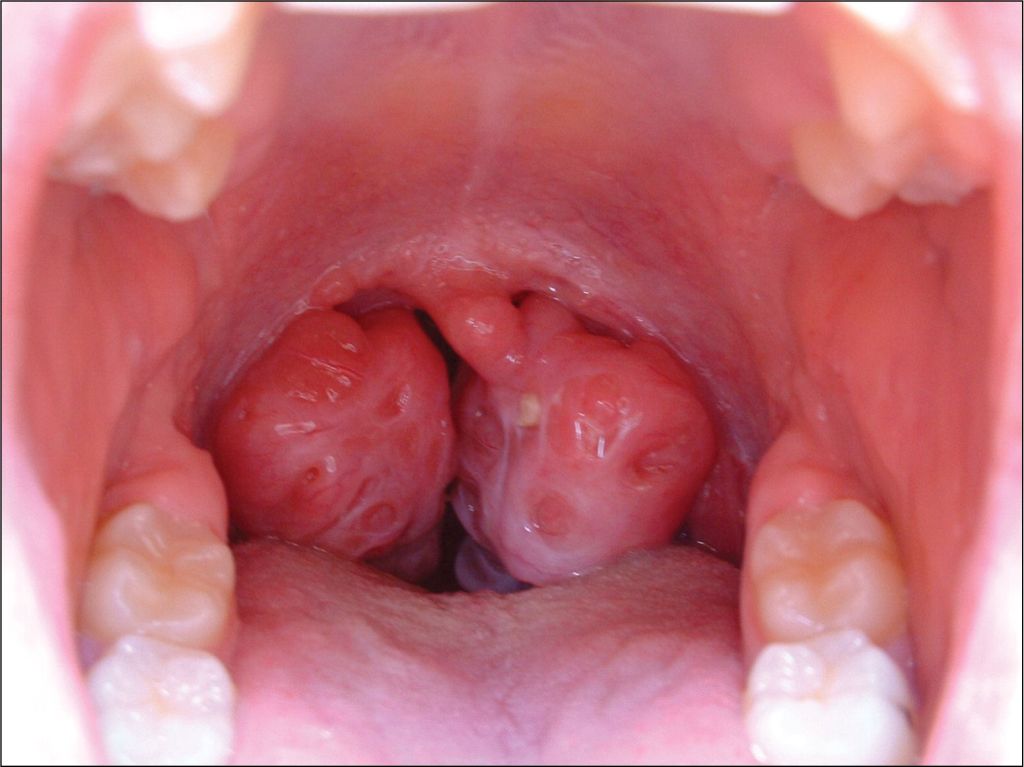

1. Tonsil dan Adenoid yang membengkak besar

Pembesaran (hypertrophy) tisu tonsil dan adenoid akan menyebabkan kedua-dua saluran pernafasan hidung dan mulut tersumbat semasa tidur. Ini akan mengakibatkan dengkur yang kuat dan seterusnya mengurangkan kualiti tidur pesakit.

Pemeriksaan yang rapi oleh pakar ENT dapat mengesan masalah anatomi seperti tonsil/adenoid bengkak atau resdung. Pembedahan membuang tonsil dan adenoid kadangkala diperlukan dalam keadaan dengkur yang serius.